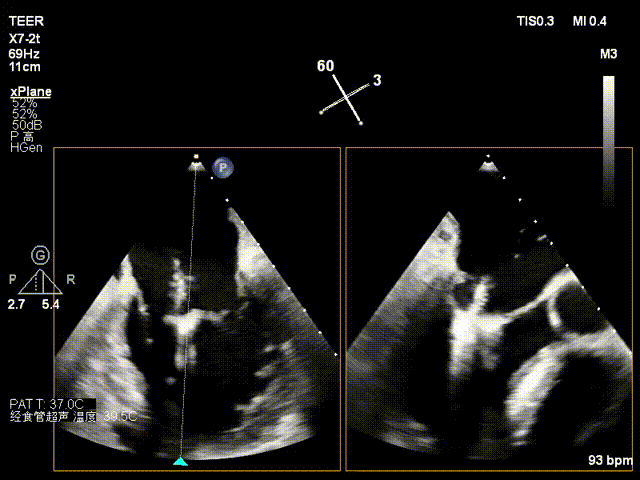

术中影像

于2偏1区置入一枚长宽夹

瓣叶捕获.

L侧无残余脱垂及反流

于M侧平行置入第二枚长宽夹

瓣叶捕获

Bouncing明显

组织桥稳定

M侧有残余脱垂及反流

于M侧植入一枚长窄夹

夹闭后残余微量功能性反流

3D评估组织桥

TMPG:5mmHg

术前静脉逆流

术后静脉逆流